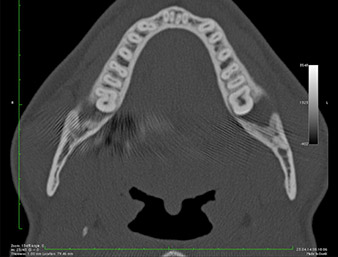

Radiografia panoramica 6 mesi dopo l'osteotomia

Fig. 1: Radiografia panoramica 6 mesi dopo l'osteotomia del dente 38 (LL8): la radix relicta si trova in prossimità del nervo alveolare inferiore.

Nell'immagine 3D (tomografia volumetrica digitale) era visibile che il residuo di radice era collocato in posizione distocaudale nella transizione dalla porzione orizzontale alla porzione ascendente della mandibola (Fig. 2).

In base all'anamnesi, il paziente (non fumatore, 26 anni) presentava probabilità molto elevate di un outcome positivo. A causa dell'indicazione della stretta vicinanza del residuo di radice al nervo alveolare inferiore nella radiografia panoramica, è stata utilizzata anche la tomografia volumetrica digitale (6).